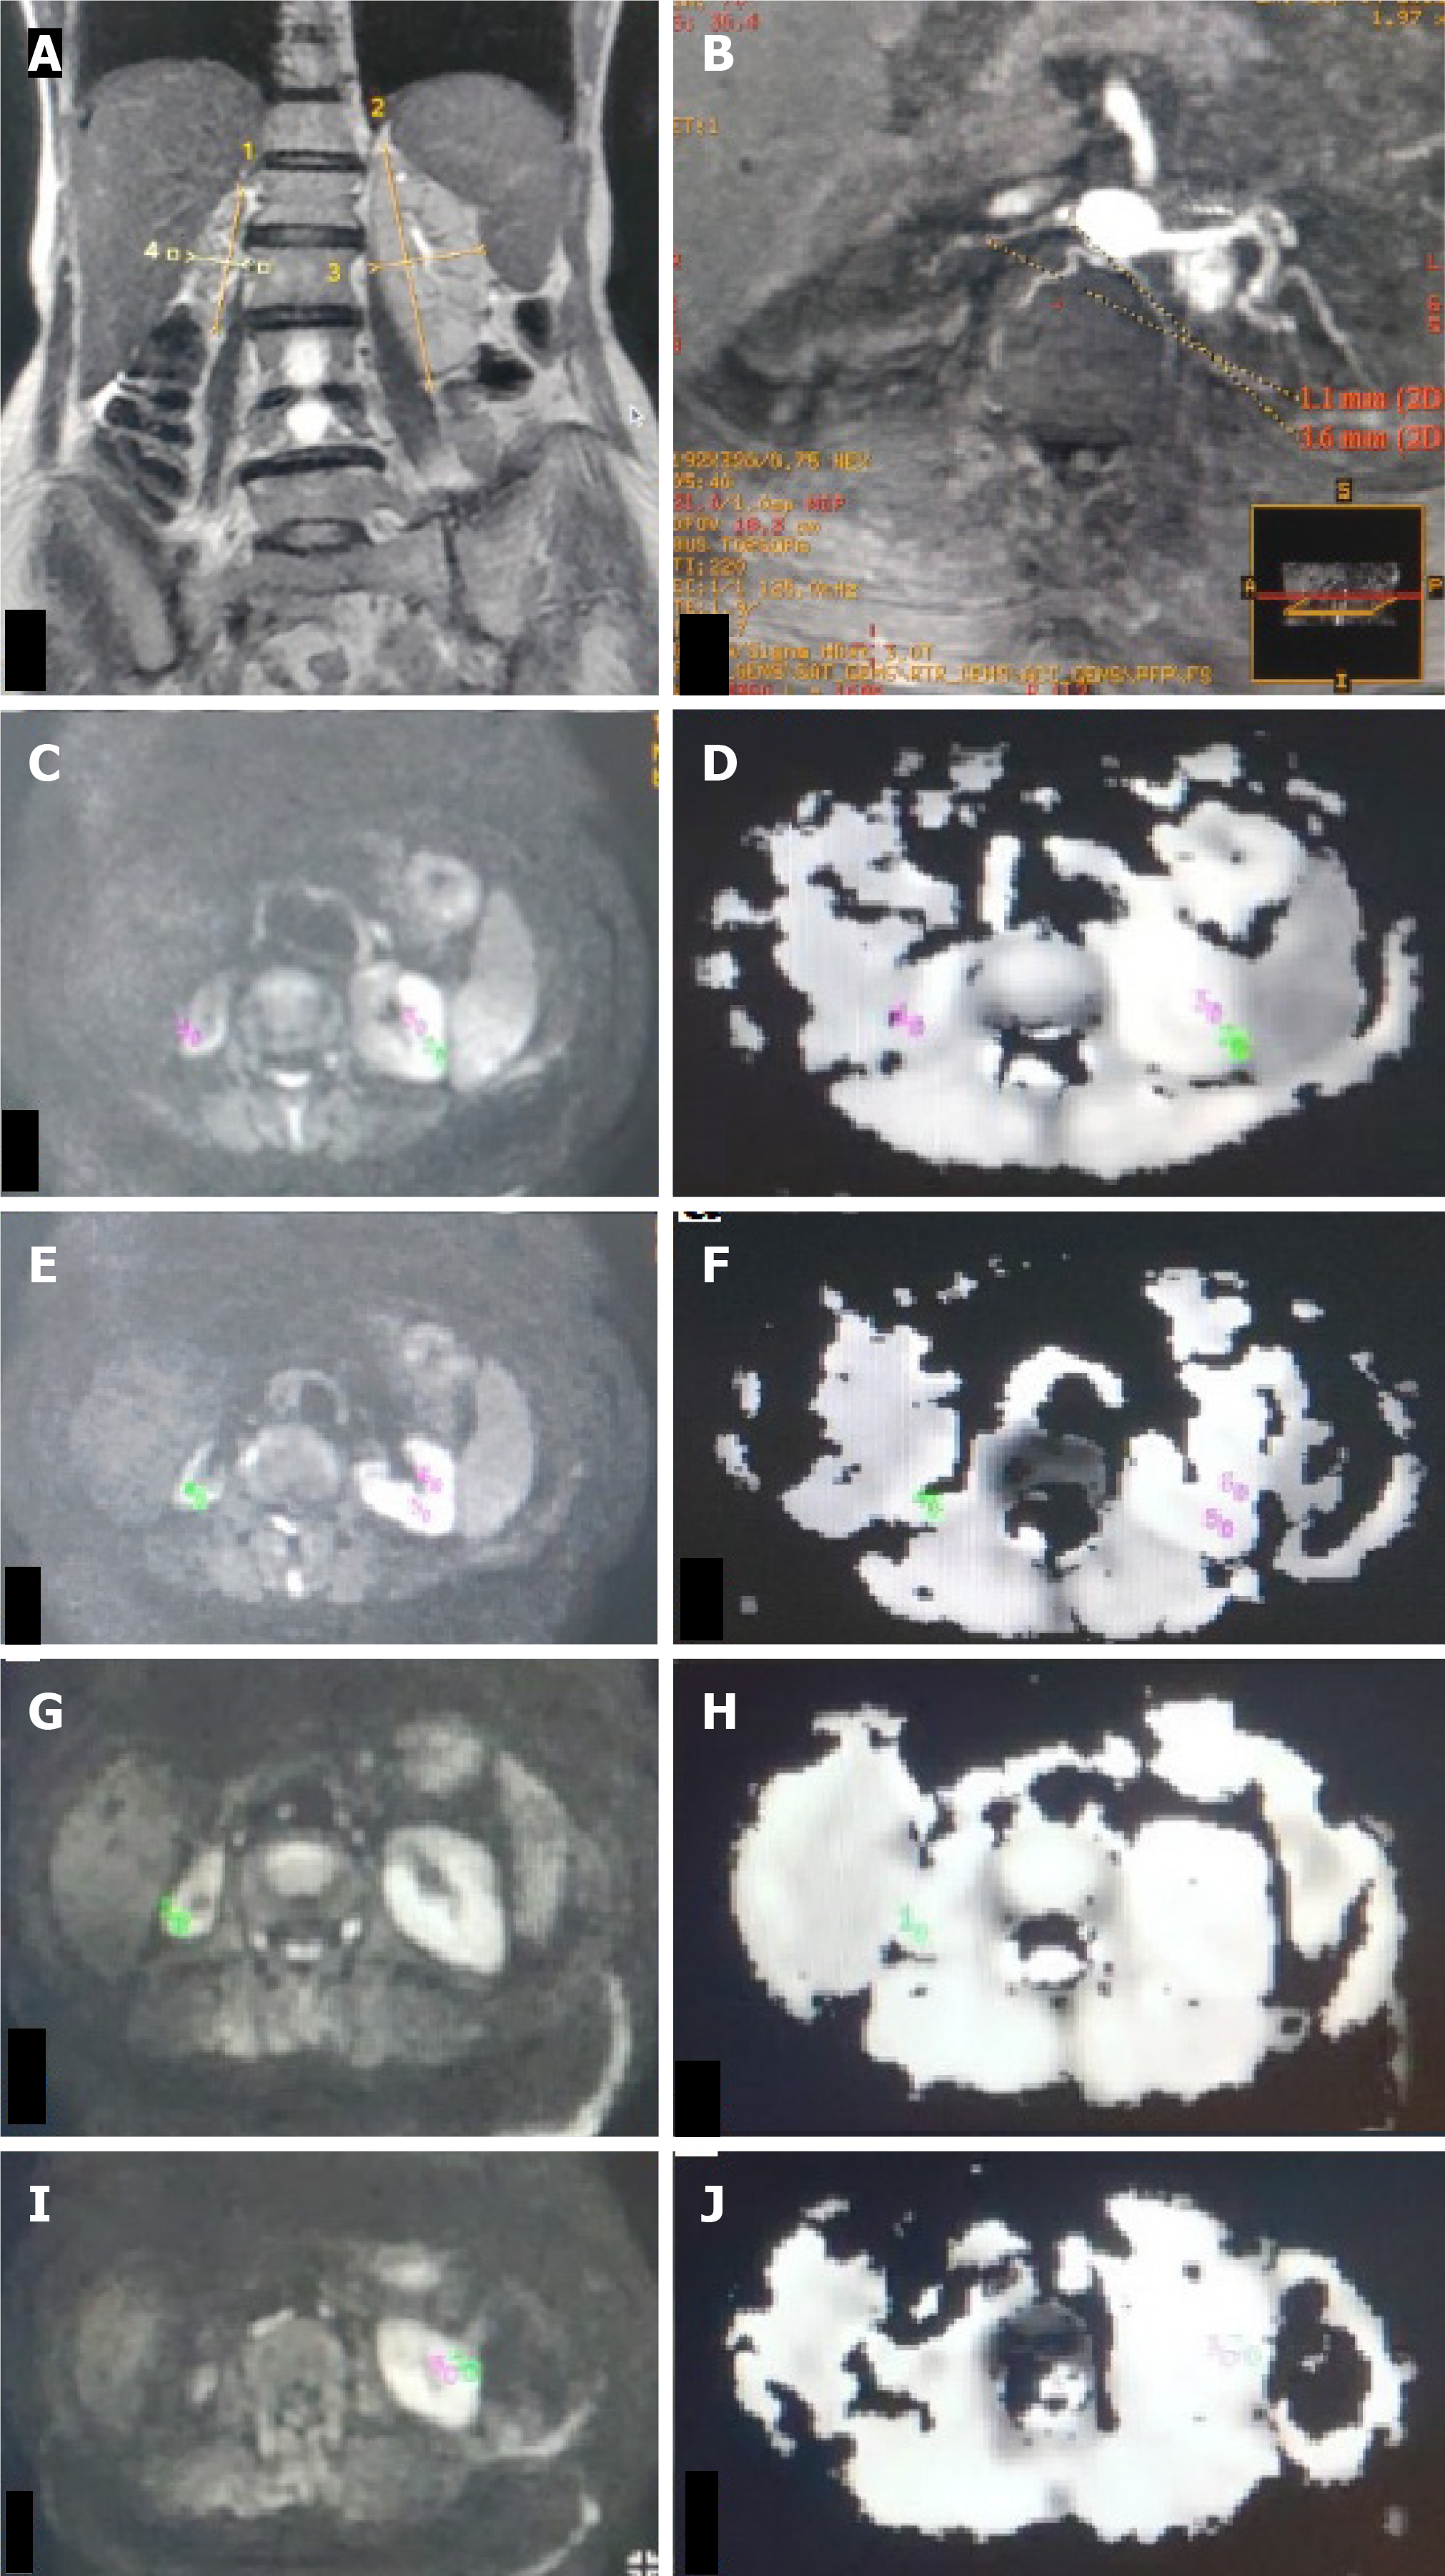

Figure 6 Unilateral renal artery stenosis with normal-sized kidney.

A: T2W magnetic resonance (MR) image (coronal plane) showing bilateral normal-sized kidneys (RK 8.6 cm, LK 10.7 cm); B: Non-contrast MR angiography (INHANCE ) in axial plane depicting severe right renal artery stenosis at the ostium; C-H: Diffusion-weighted MR image (C, E, G, I) in the axial plane with corresponding apparent diffusion coefficient (ADC) map (D, F, H, J) of bilateral kidneys showing manually drawn region-of-interest (ROI) placed in the upper (C, D), middle (E, F) pole of bilateral kidneys, lower (G, H) pole of the right kidney and lower (I, J) pole region of left kidney. The ROI is placed in the cortex and medulla on both sides. Mean cortical ADC and medullary ADC values of the right kidney were 165 × 10-3 mm2/s and 1.63 × 10-3 mm2/s, respectively. Mean cortical ADC and medullary ADC values of the left kidney were 198 × 10-3 mm2/s and 1.84 × 10-3 mm2/s, respectively.